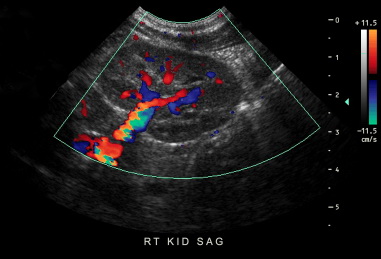

Ultrasound is a non-invasive, painless procedure that simply involves placing a probe over the heart or abdomen to give us a peek inside. Ordinary X-rays give us a general layout of the abdomen but it does not allow us to look inside the organs themselves. They give us a two dimensional image of a three dimensional structure. Ultrasound allows us to completely interrogate the inside of each organ to study disease. X-rays however are still important and are used to correlate with the ultrasound images to complete the visual portion of the study. Anesthesia is not required. In some cases, mild sedation or analgesia might be necessary.

With ultrasound, we are able to do studies as simple as pre-natal puppy checks up to advanced cardiac imaging. All of our cardiac studies are interpreted by a Board Certified Cardiologist and most abdominal studies are read by a Board Certified Radiologist. This gives us the most competent and complete information from the most competent experts. The images are sent over the internet to the appropriate specialist who may be located anywhere in the United States. There are some cases where we will refer you directly to a specialist depending on the type and severity of the illness however, in most cases, providing ultrasonography here offers an efficient, convenient and cost effective means of getting diagnostic questions answered quickly - often while you wait.